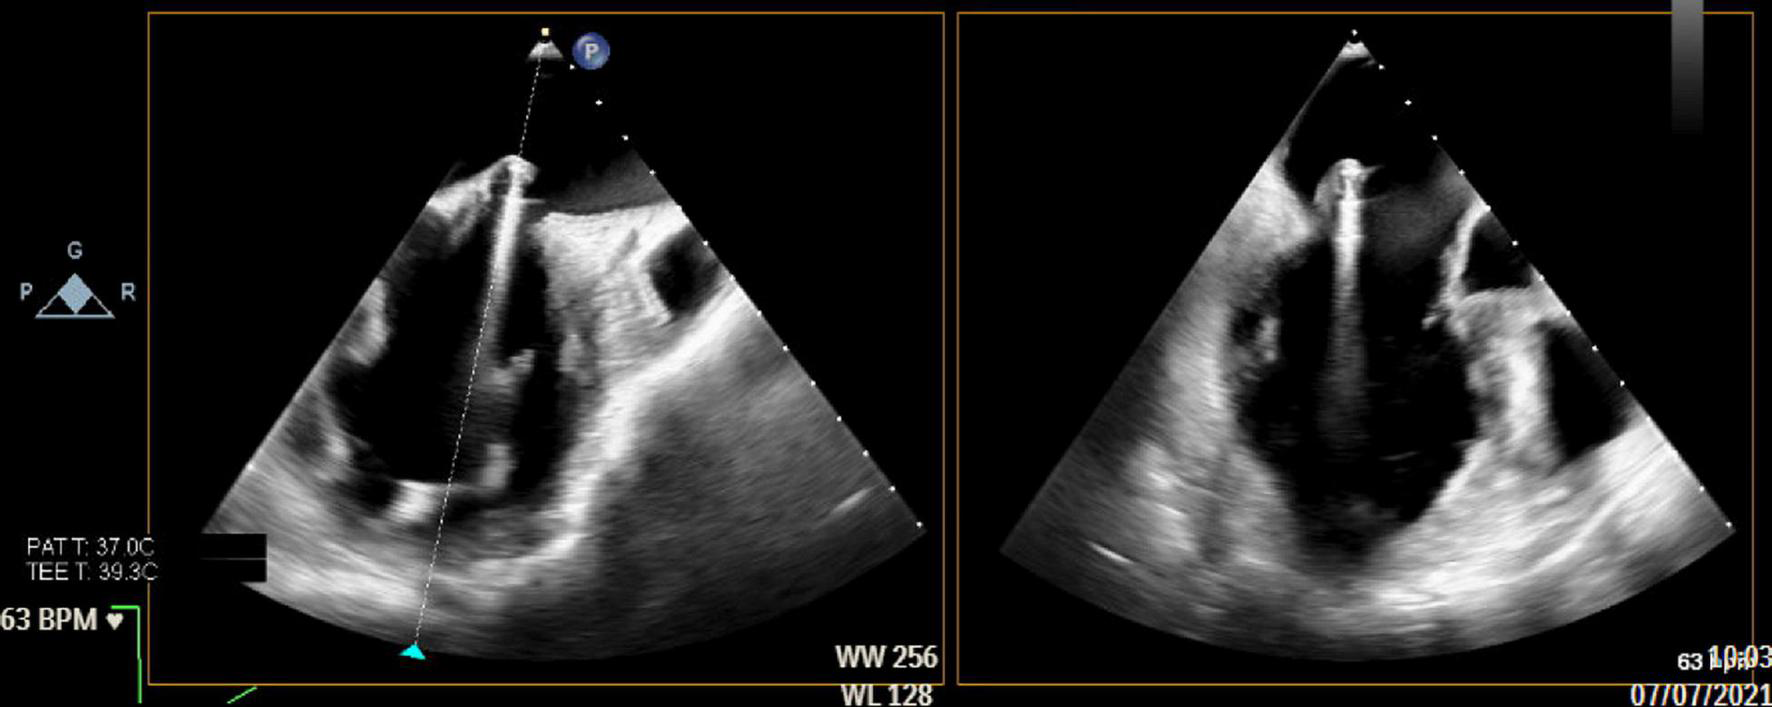

Transesophageal Echocardiography-Guided Introduction of Introducer

The entry-location for the insertion of the introducer must be identified on the epicardium (Figure 4). This should be approximately 3 cm basal from the true apex and 1 cm lateral to the left anterior descending (LAD) coronary artery (i.e., between the LAD and the diagonal branches). The chosen entry-location can be checked with a finger-indentation test on the ventricular wall on TEE to ensure that the introducer will be inserted just apical to the base of the anterolateral papillary muscle. The ME mitral commissural view best visualizes the papillary muscles with the corresponding native chords (the anterolateral papillary muscle is located in the right side of the image).

The hemostatic introducer (with 14-Fr external and 12-Fr internal diameter) is now ready to be inserted using a 0.035” guidewire. Insertion of the introducer should be visualized simultaneously in both the intercommissural and LAX views. On the mitral commissural view, the medial to lateral view of the mitral valve (P3-A3-A2-A1-P1) is seen from left to right. On the long-axis view, the posterior to anterior view (P2-A2) is visualized from left to right.

When the delivery system has reached the targeted location, the atraumatic end effector on the distal tip of the delivery system should be used to stabilize the leaflet throughout the cardiac cycle on the underside of the pMVL at the targeted implantation site (Figure 5) (37). A Valsalva test should simultaneously be performed by the anesthesiologist. When the location is satisfactory according to the surgeon and imaging cardiologist, the delivery system can be deployed. When the delivery system is deployed, a 21-gauge needle with a prewrapped ePTFE double-helical knot (50 winds) penetrates the pMVL. After deployment, the needle is automatically withdrawn and the ePTFE coil is tightened, forming a double-helix knot on the atrial leaflet surface (36, 37).

FIGURE 5

The end effector is used to stabilize the HARPOON device on the underside of the pMVL at the targeted implantation site. pMVL, posterior mitral valve leaflet.